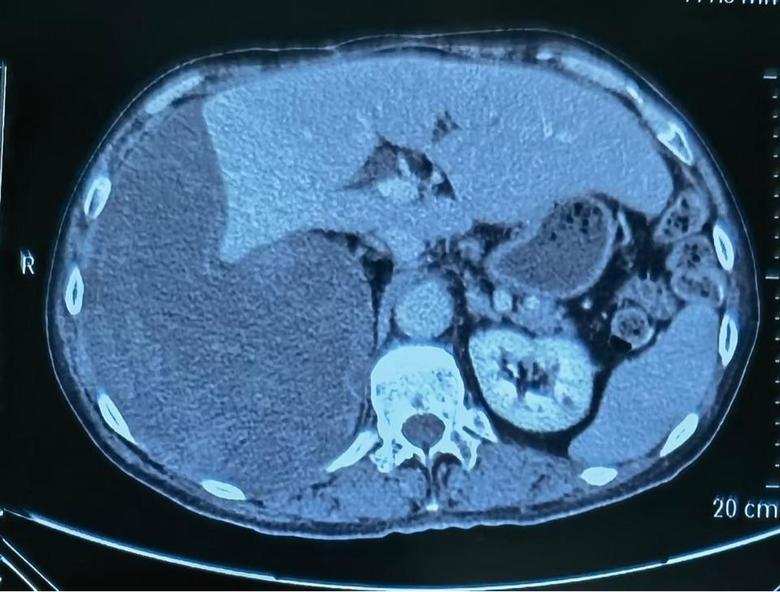

病例1

今日下午,2例巨大腹膜后肿瘤手术在我科顺利开展,腹膜后肿瘤发病率低,手术难度大,手术风险大,国内开展相关手术单位为数不多,我院腹膜后肿瘤手术量连续数年位居国内前列,在腹膜后肿瘤领域团队具有丰富经验,巨大腹膜后肿瘤手术开展,表明该类手术在我院已经成为常态。并且将继续保持国内在领先水平。